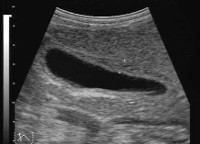

УЗИ желчного пузыря является наиболее информативным методом диагностики дискинезии. УЗИ помогает визуализировать форму и размеры желчного пузыря, характер его содержимого, наличие или отсутствие включений, перегибов и перетяжек. Выявление деформаций желчного пузыря повышает вероятность диагностирования его дискинезии. Также во время ультразвукового исследования оценивается сократительная способность стенок пузыря.